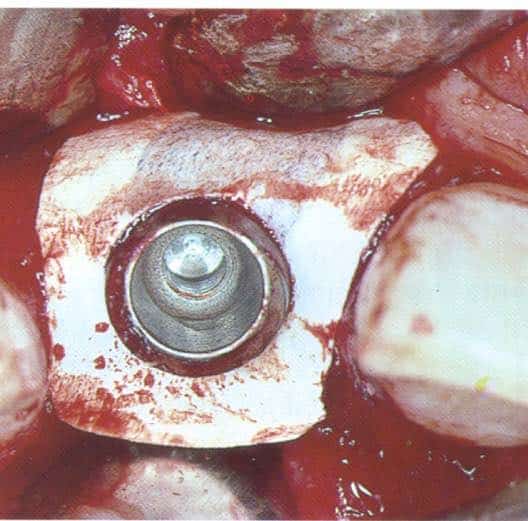

Tissue level implants (some of them hollow cylinder), back then the “ITI system”, were placed in fresh extraction sockets, augmented with GBR and let to heal transmucosally and later be restored with solid abutments. Today I could have considered this impossible, if it wasn’t for a well documented study. The year was 1996, in Bern by Brägger, Hämmerle and Lang. Twenty seven years later, all three were part of the ITI Consensus in Lisbon which accepted A1 immediacy as treatment of choice.

Likewise, the attempt to bring immediacy into the mainstream around 2004 proved to be a bridge too far. The commercial vehicle to materialise the promises of immediacy was soon launched and it was no other than implants designed for placement in extraction sockets aiming to receive immediate provisionals and promising to preserve tissue. Nobel Perfect and Nobel Direct, were two implants launched and marketed as the “immediacy” implants. They were one-piece implants with certain features that were expected to optimise outcomes of placement in fresh extraction sockets. Among these was the provision for a cement retained crown, the lack of an implant-abutment “gap” and also the coronal extension of rough surface, which was envisioned to enhance the attachment of the soft tissue. For this purpose and also to support interproximal papilla, Nobel Perfect had scalloped margins of the rough surface. The spatial positioning of an immediate implant at that time was also not perceived as today; there was a misguided view that filling the socket with titanium was the element which lead to bone preservation. This might be the principle behind another immediacy implant, around that time from Straumann, the TE implant which was a tissue level implant with characteristically wider coronal part.